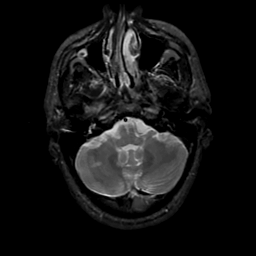

MR Study #20 October 6, 1991 -- Slice #10

[Home][Help][Clinical][Tour 1][Tour 2] Slice 10